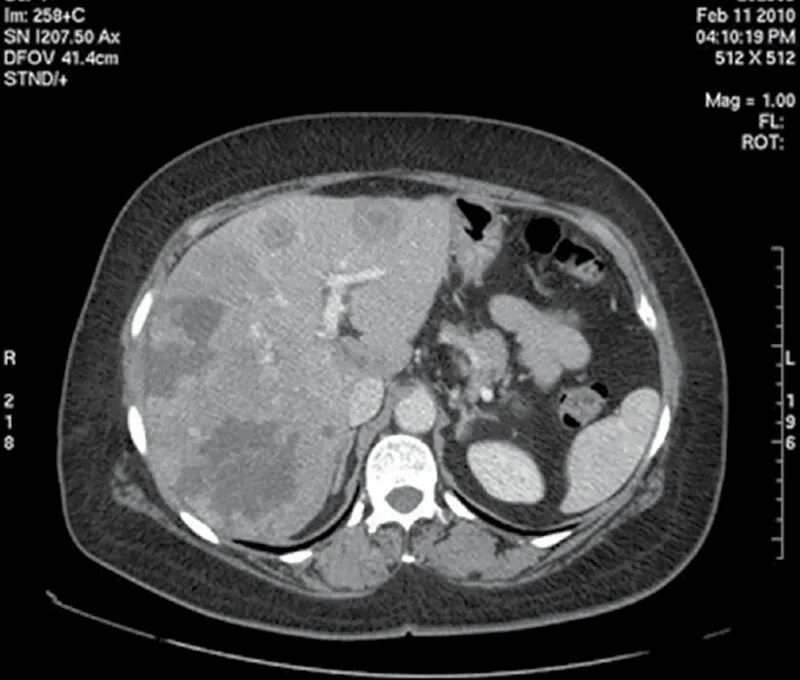

Метастазы в печени прогноз срока жизни